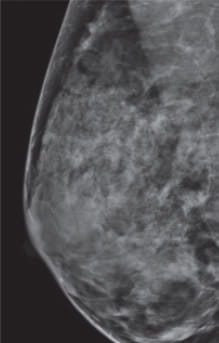

Breast Density Scattered Areas of Fibroglandular Density

Category B: Scattered areas of dense breast tissue